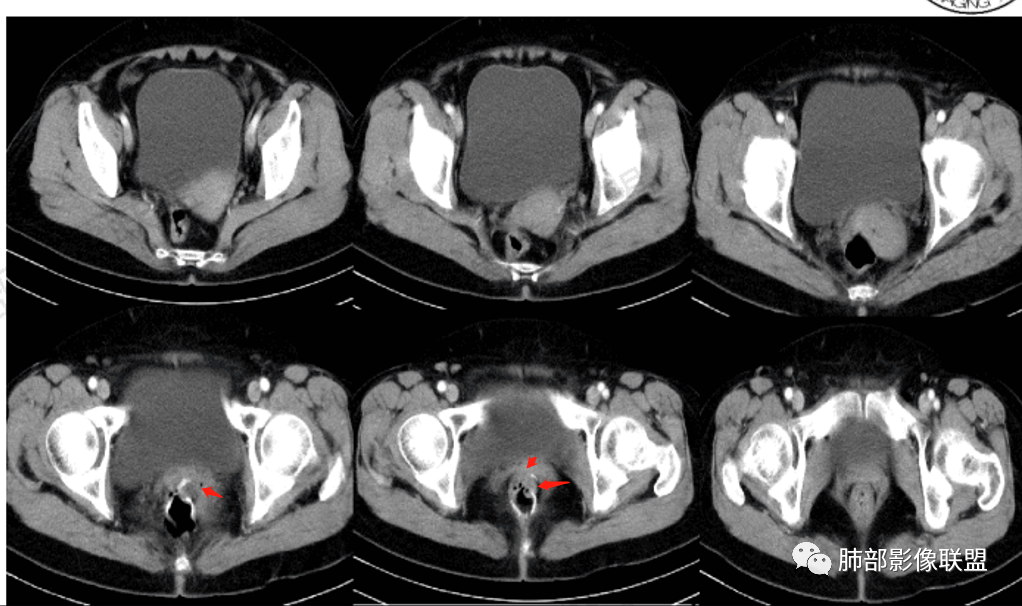

△直肠术区壁增厚,外壁欠清,局部强化偏低,转移瘤确实要考虑

△宫颈局部确实有受压的迹象

△直肠术区局部肠壁增厚了,增强局部有低强化灶,直肠确实符合复发的表现,还是要恶性首选